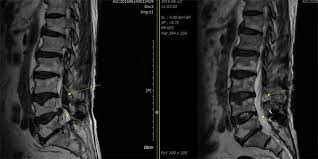

허리협착증은 척추 속 신경이 지나가는 통로인 '척추관'이 좁아지면서, 신경을 눌러 통증이나 저림 등의 증상을 유발하는 질환입니다.

- 요추관협착증은 주로 허리 부분(L3~L5)의 협착으로 인해 발생합니다.

- 퇴행성 변화, 즉 디스크, 인대비후, 관절돌기 비대 등이 원인이 됩니다.